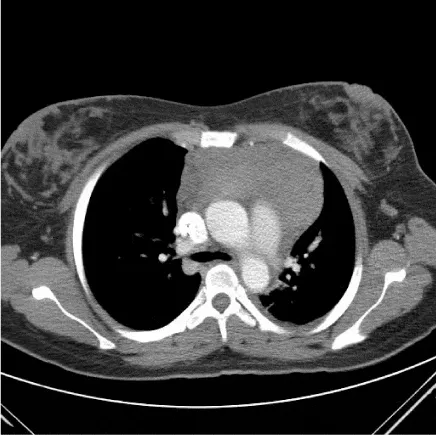

Case 2 is a 24 year old female who presented to an outside hospital in March of 2012 with left sided chest pain. Routine CBC was obtained which showed a WBC count of 20,100 per microliter with 46% lymphoblasts (Figure 4). A CT of the chest was performed which revealed an anterior mediastinal mass measuring 3.8 by 8.2 cm (Figure 5). There was no other lymph node enlargement and splenomegaly. She was referred to a hematologist where flow cytometry on the peripheral blood showed a T-cell lymphoproliferative process comprising 60% of the lymphocytes. She subsequently underwent bone marrow aspiration and biopsy which was suboptimal and non-diagnostic. The patient was then seen by a hematologist at this institution who referred her to thoracic surgery for a VATS procedure with biopsy. Pathology from this specimen showed T lymphoblastic lymphoma/leukemia with a high Ki-67 proliferation fraction of 95-98%. She underwent repeat bone marrow aspiration and biopsy that showed involvement by a precursor T-cell gamma-delta acute lymphoblastic leukemia with greater than 80% lymphoblasts (Figure 6). Flow cytometry from this specimen showed a population of lymphoblasts that expressed CD2, CD3, CD4, CD5, CD8, CD10 and the TCR gamma-delta (Figure 7).

Approximately 4 months following her initial diagnosis the patient received conditioning with TBI 12 Gy administered in 6 fractions over 3 days and Cyclophosphamide 35 mg/kg for two doses. Post-transplant graft-versus-host disease prophylaxis included cyclophosphamide 50 mg/m2 given on day +3 along with tacrolimus and mycophenolate mofetil started day 5. Post-transplant complications included neutropenic fever, pneumonia and acute renal failure which resolved with treatment. During her taper of tacrolimus she developed stage 1 grade 1 acute skin GVHD that was treated with topical agents. Her rash resolved and her tacrolimus taper was completed by day + 240. Bone marrow biopsy performed 3 months, 6 months and 12 months following transplant showed no evidence of recurrent leukemia. Chimerism studies showed 100% CD3 and 100% CD15 donor cells. CT scan of the chest showed complete resolution of the anterior mediastinal mass. The patient was well until approximately 18 months post-transplant when routine PFTs showed mild obstructive changes concerning for bronchiolitis obliterans. Over the subsequent 2 months she developed decreased ROM in her wrist and elbow joints bilaterally and sclerodermal skin changes consistent with chronic GVHD. Initiation of treatment with prednisone, sirolimus and Rituximab was recommended but was declined by the patient. She continues to be in complete remission from the standpoint of her leukemia with stable chronic GVHD findings.